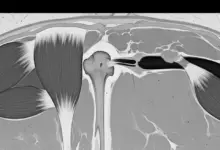

Vamos entender primeiramente como a dor no ombro se conecta com a dormência nas mãos. Então, essa dinâmica envolve o plexo braquial, uma rede complexa de nervos.

Esses nervos vão da coluna cervical até as mãos, portanto, qualquer problema nessa região pode causar dor e dormência não apenas onde está localizado o problema.

A Anatomia do Plexo Braquial e Sua Influência na Sensibilidade

Os nervos do plexo braquial são fundamentais para mover e sentir nossos braços e mãos, logo, se o ombro está lesionado, pode afetar o plexo braquial.

Consequentemente, isso pode causar dor no ombro e sintomas como dormência nas mãos.